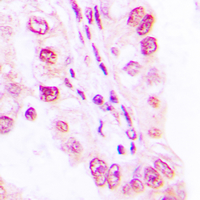

- Immunohistochemical analysis of SAP49 staining in human lung formalin fixed paraffin embedded tissue section. The section was then incubated with the antibody at room temperature and detected using an HRP conjugated compact polymer system. DAB was used as the chromogen. The section was then counterstained with haematoxylin and mounted with DPX.